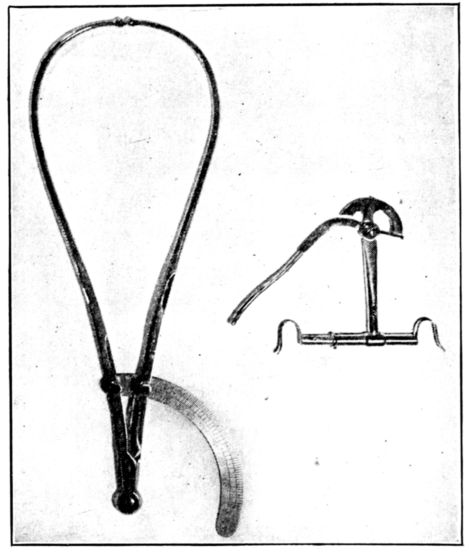

25In considering the question of pelvimetry, we find that there are both external and internal measurements to be taken, all for the purpose of estimating as accurately as possible the shortest diameter of the inlet through which the baby must pass. (Fig. 5.)

Fig. 5.—Two types of pelvimeters frequently used in taking measurements of the pelvic inlet and outlet.